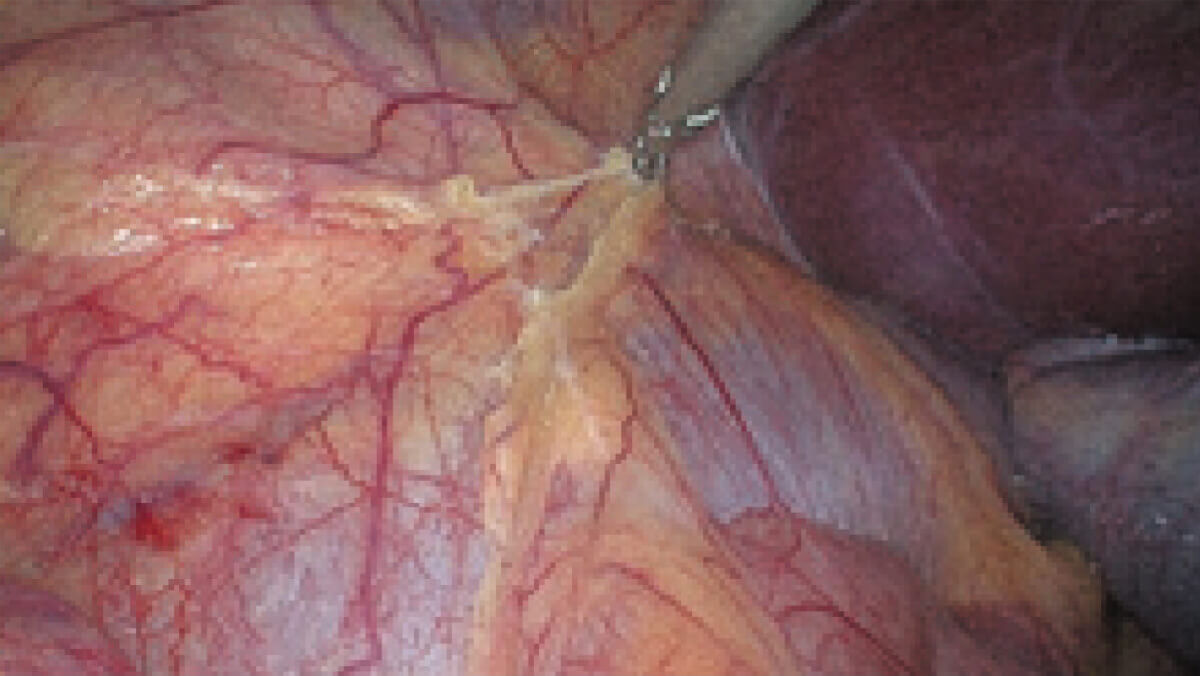

白光与荧光像素级匹配

结合自研镜体齐焦技术

多种成像模式随意切换不移焦

表面细节不遮盖

边界清晰,利于切缘评估

细微结构无伪影

避免术中误伤

荧光信号强弱分明

精准辅助临床决策